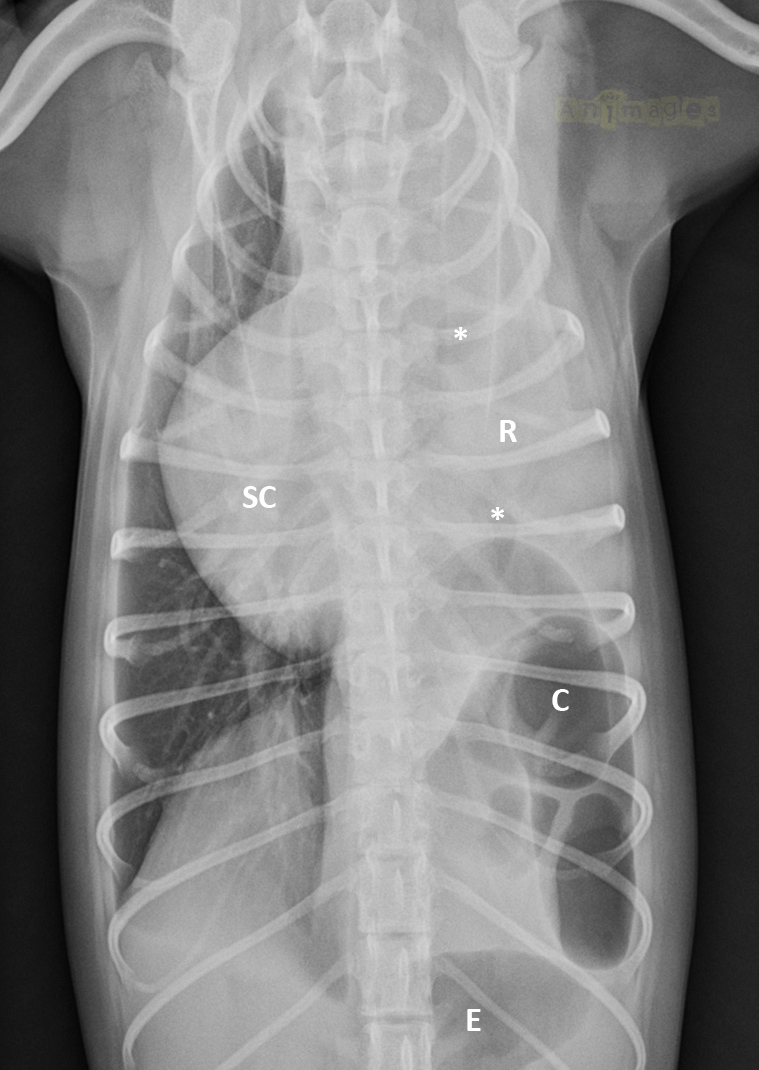

VD-annot